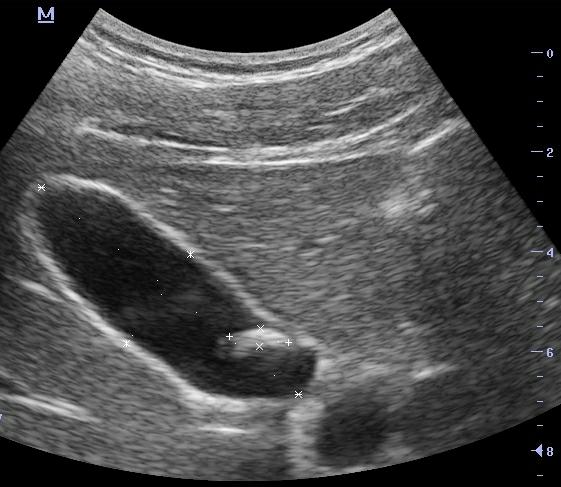

Лечение данного заболевания имеет свои особенности. Существует несколько подходов к терапии и дальнейшей работе с зараженным протоком (важно уделять внимание протокам даже после завершения терапии). Начало лечения должно быть связано с проведением ультразвукового обследования (УЗИ).

После постановки диагноза необходимо проводить УЗИ каждые 6 месяцев во время общего лечения и раз в год для контроля состояния организма пациента.

Лечение начинается с проведения ультразвукового исследования.